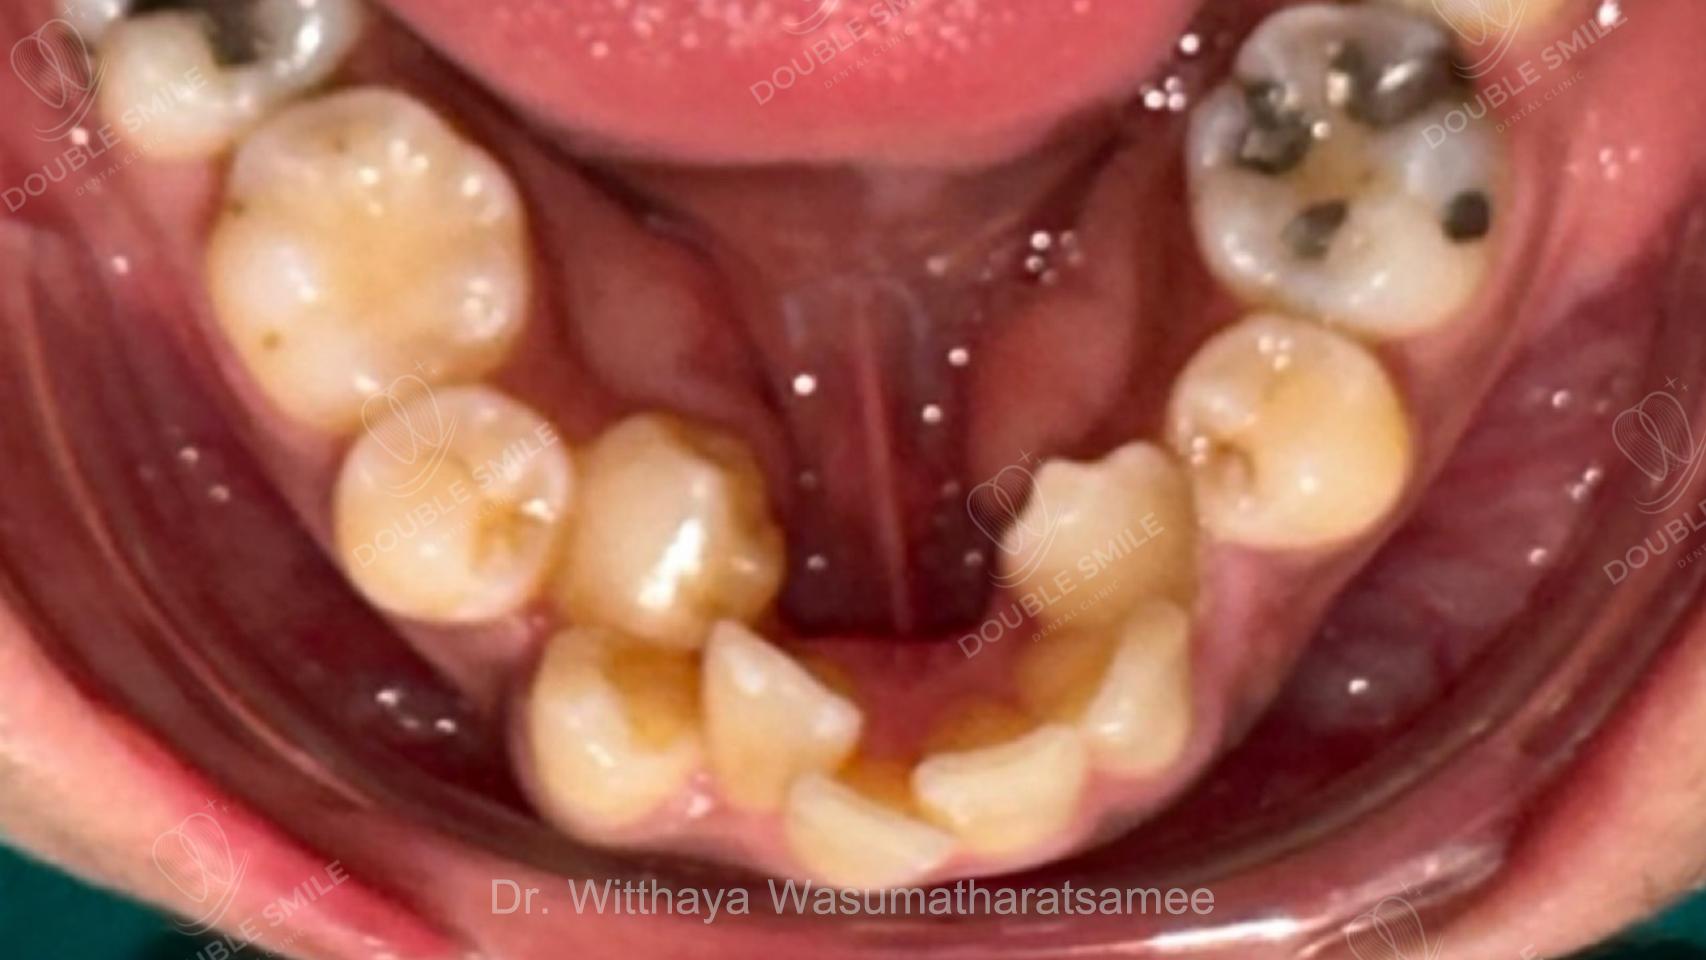

เคสรีวิวที่ 55

Before

Case Review

Before & After